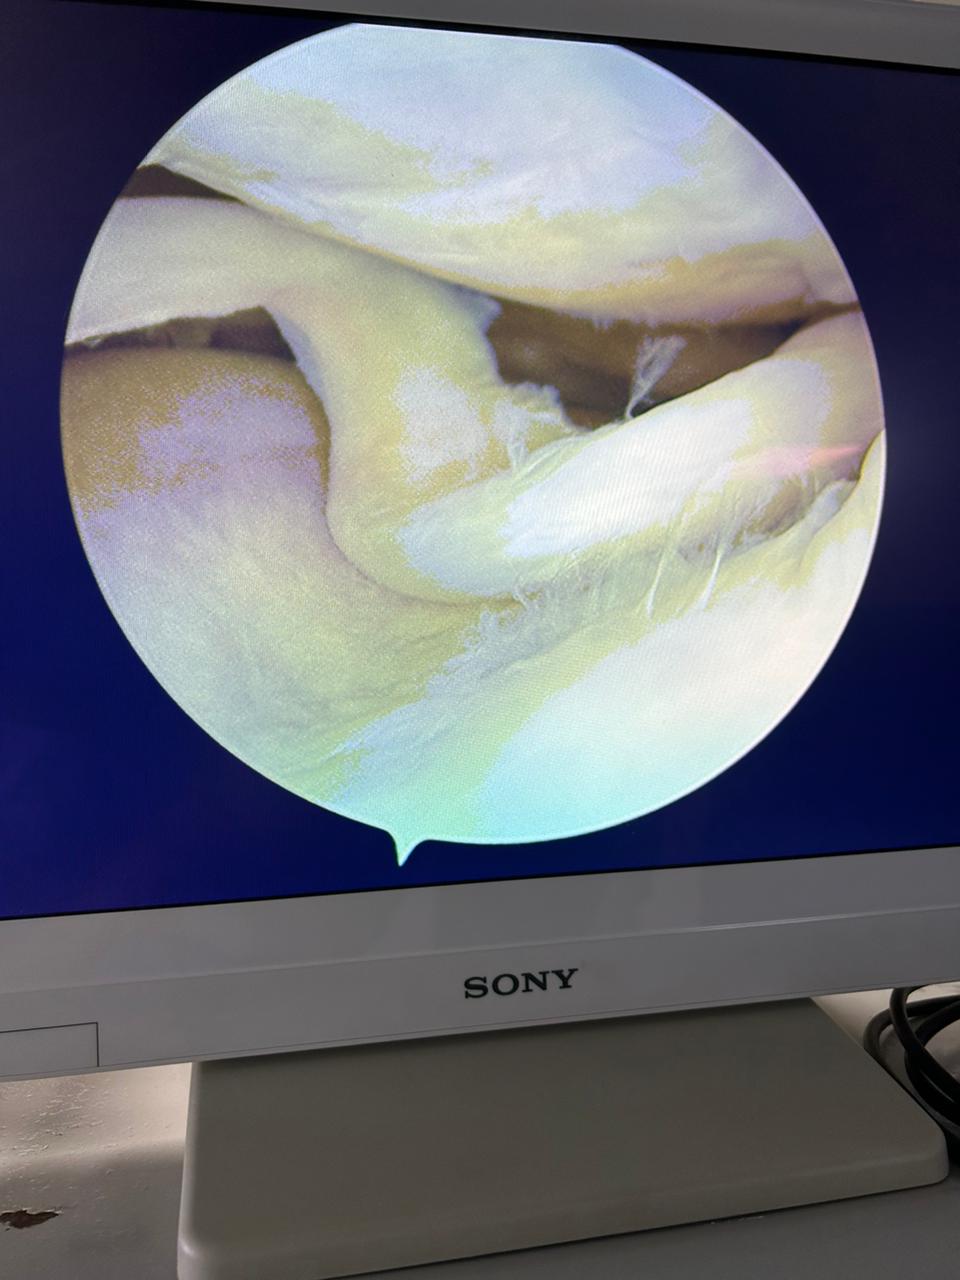

Nowadays,there is no need to remove the meniscus , in the latest medical advancement, and this “ Saving the Meniscus “, we are regularly following in our Practice. It can be saved by Latest all inside Technique of Meniscus repair , by key hole surgery as seen in Videos and photos.